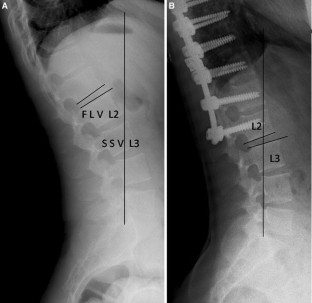

Distal junctional kyphosis (DJK) is a major instrumentation-related complication after the surgical correction of Scheuermann kyphosis (SK). The exact criteria to avoid DJK have been controversial. It has been recommended to include the SSV into the fusion by some authors, while others suggest that fusion to FLV is sufficient. The purpose of this study was to investigate the occurrence of DJK in relation to distal fusion level selection in SK surgery by investigating the relationship between the sagittal stable vertebra (SSV), first lordotic vertebra (FLV), and the lowest instrumented vertebra (LIV).

Mean preoperative kyphosis angles were 77.2°, 73.4°, and 76.7° in groups 1, 2, and 3, respectively (p = 0.281), which decreased to 38.1°, 37.3°, and 37.8° postoperatively at final follow-up (p = 0.988). Mean follow-up time was 28.3 months. Correction amounts were similar between the groups (p = 0.409). 3 patients in SSV group, 5 patients in FLV group, and 3 patients in SSV-FLV group developed DJK, which was statistically insignificant. The C7 sagittal plumbline, lumbar lordosis, and pelvic parameters were not significantly different before or after surgery between the groups. Preoperative and postoperative results of SF-36 questionnaire were similar in all the groups. None of the patients who had DJK required revision surgery during the follow-up time.

Proper selection of distal fusion level is important in order to prevent DJK after SK surgery. According to this study, it is not necessary to extend the fusion down to the SSV. Fusion to FLV is sufficient and saves a level.